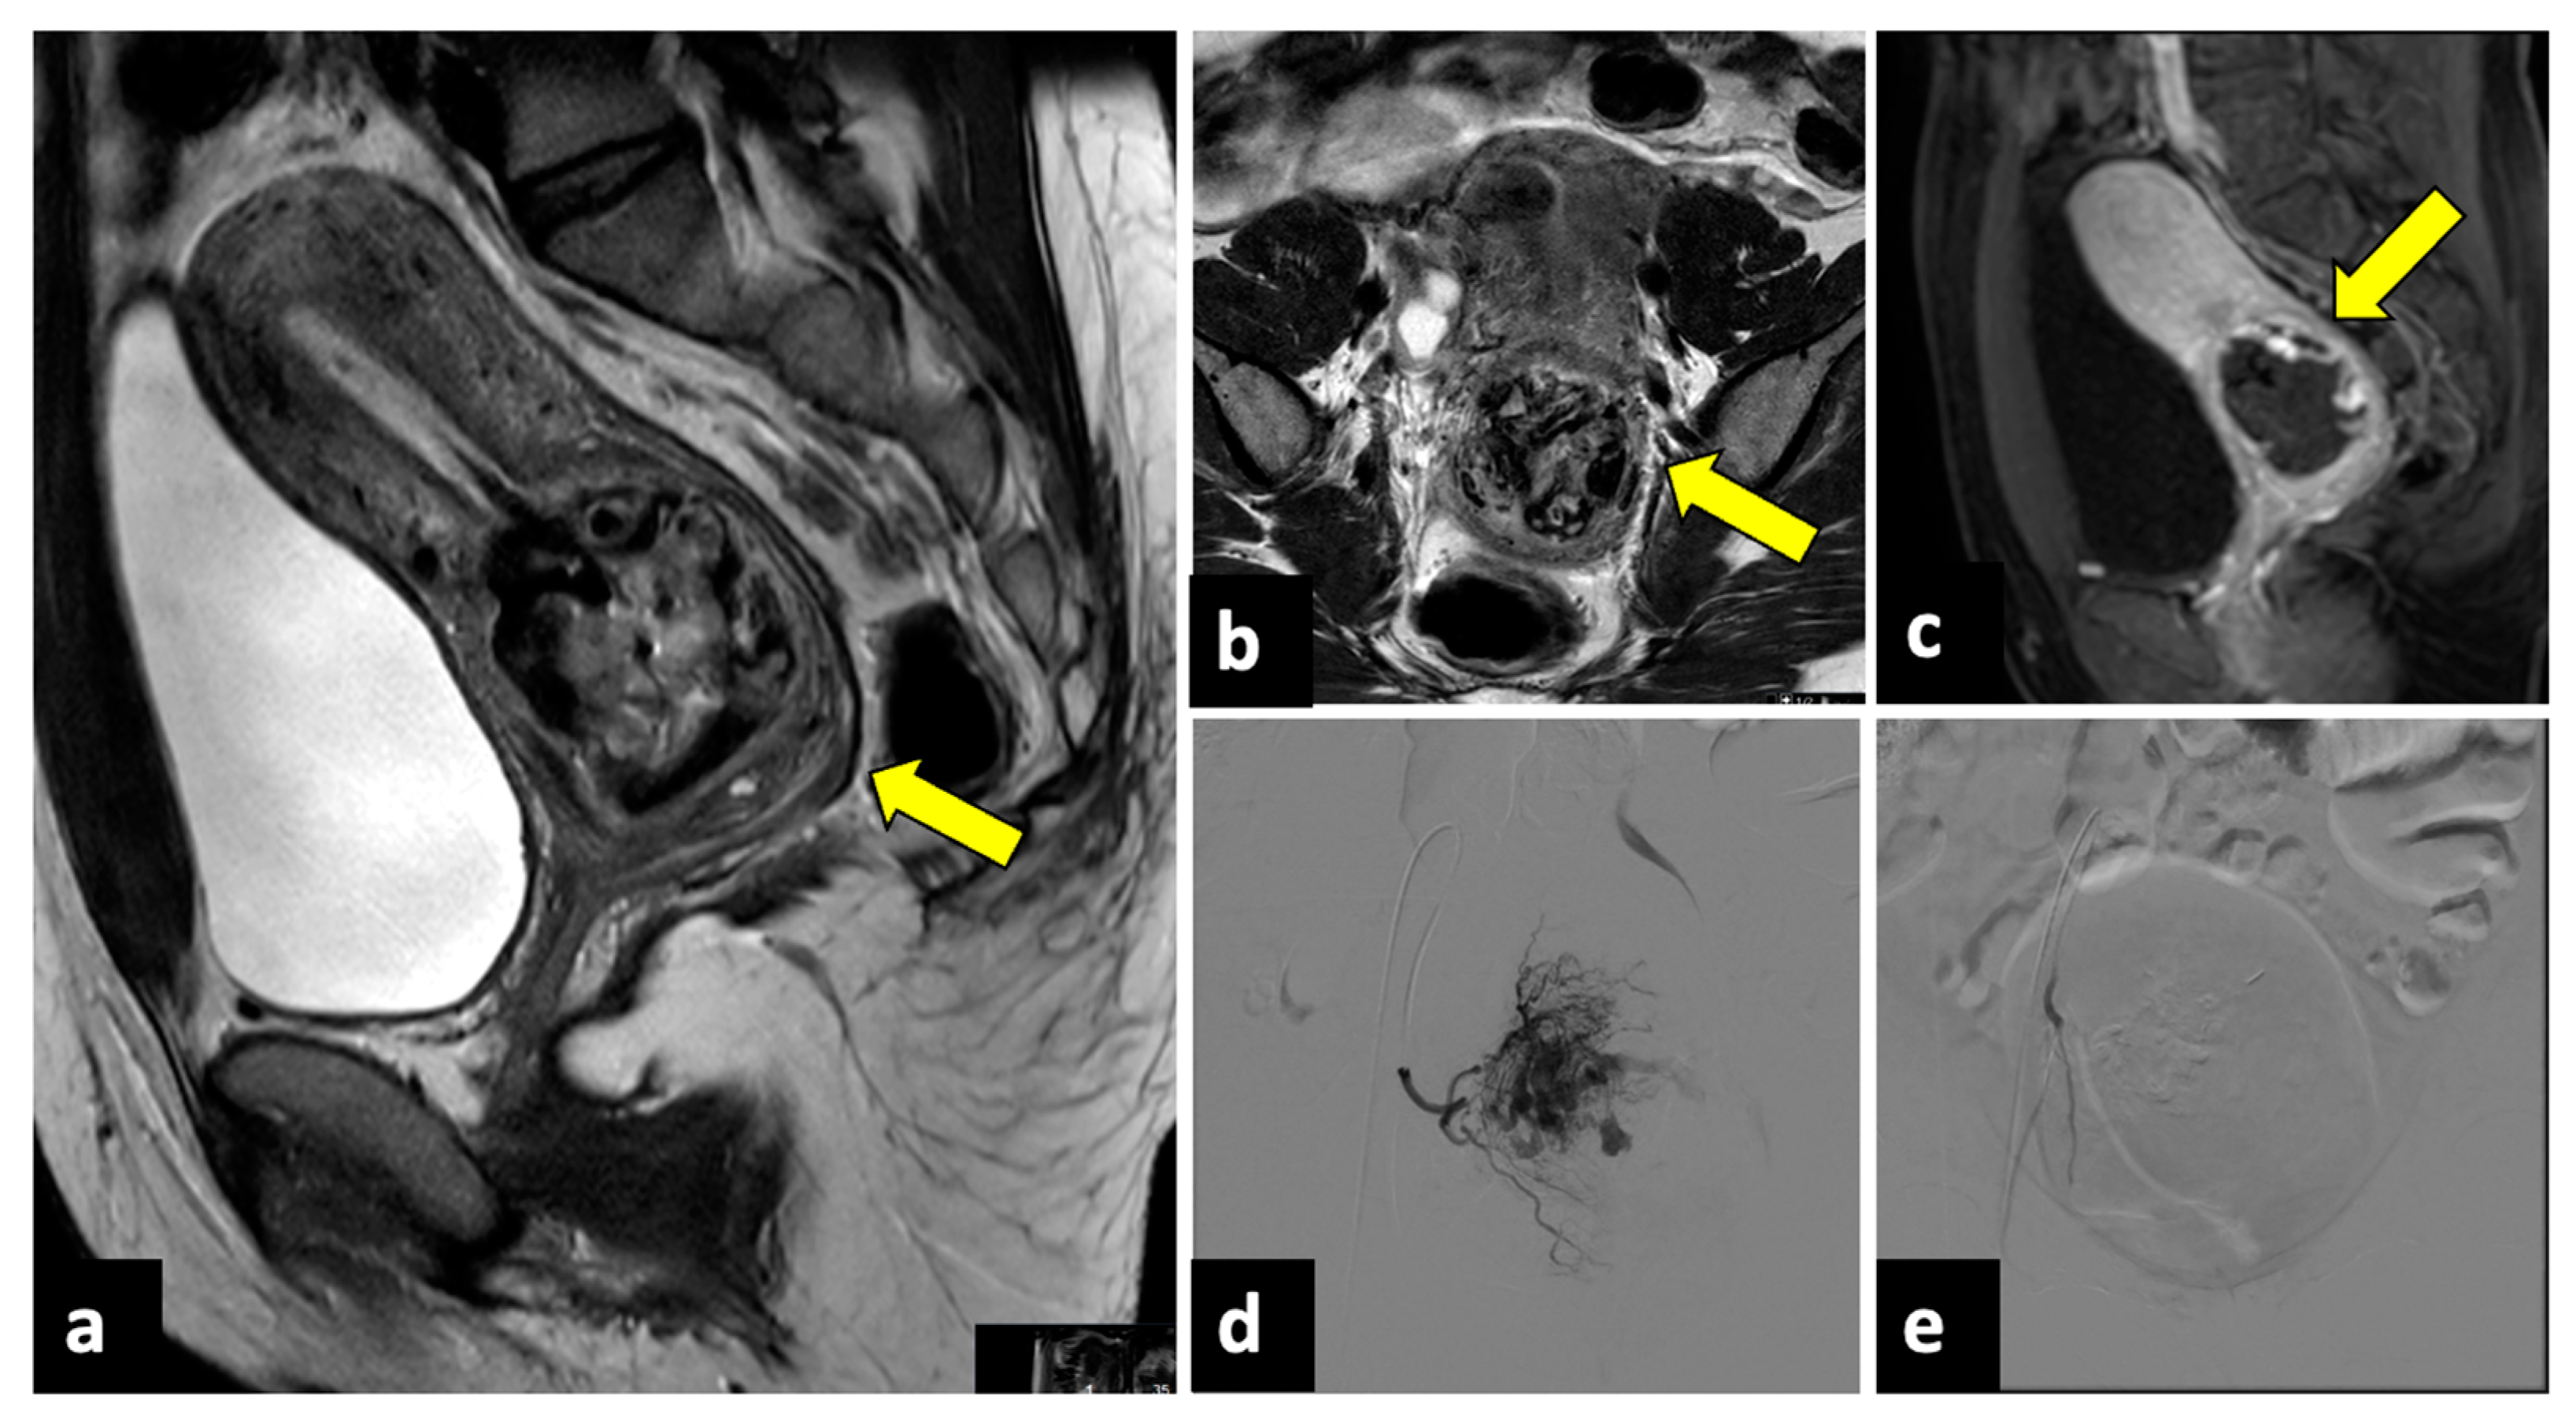

2.4. Complicated Uterine Leiomyomas

- Mathew, R.P.; Francis, S.; Jayaram, V.; Anvarsadath, S. Uterine Leiomyomas Revisited with Review of Literature. Abdom Radiol 2021, 46, 4908–4926. [Google Scholar] [CrossRef] [PubMed]

- Kubik-Huch, R.A.; Weston, M.; Nougaret, S.; Leonhardt, H.; Thomassin-Naggara, I.; Horta, M.; Cunha, T.M.; Maciel, C.; Rockall, A.; Forstner, R. European Society of Urogenital Radiology (ESUR) Guidelines: MR Imaging of Leiomyomas. Eur. Radiol. 2018, 28, 3125–3137. [Google Scholar] [CrossRef]

- Takeuchi, M.; Matsuzaki, K.; Bando, Y.; Harada, M. Evaluation of Red Degeneration of Uterine Leiomyoma with Susceptibility-Weighted MR Imaging. Magn. Reson. Med. Sci. 2019, 18, 158–162. [Google Scholar] [CrossRef]

- Ohgiya, Y.; Seino, N.; Miyamoto, S.; Takeyama, N.; Hatano, K.; Munechika, J.; Ishizuka, K.; Hirose, M.; Ohike, N.; Hashimoto, T.; et al. CT Features for Diagnosing Acute Torsion of Uterine Subserosal Leiomyoma. Jpn. J. Radiol. 2018, 36, 209–214. [Google Scholar] [CrossRef]

- Dhillon, M.S.; Garg, A.; Sehgal, A.; Bhasin, S. Torsion of a Huge Subserosal Uterine Leiomyoma: A Challenging Case of Acute Abdomen. SA J. Radiol. 2023, 27, 2641. [Google Scholar] [CrossRef]

- Magro, M.; Gafson, I. Postpartum Pyomyoma: A Rare Complication of Leiomyoma. J. Obstet. Gynaecol. 2014, 34, 202–203. [Google Scholar] [CrossRef] [PubMed]

- Delbos, L.; Laberge, P.Y.; Lemyre, M.; Maheux-Lacroix, S. Pyomyoma After Uterine Artery Embolization: Laparotomy Avoided by In-Bag Morcellation. J. Minim. Invasive Gynecol. 2019, 26, 175–177. [Google Scholar] [CrossRef] [PubMed]

- Ono, H.; Kanematsu, M.; Kato, H.; Toyoki, H.; Hayasaki, Y.; Furui, T.; Morishige, K.; Hatano, Y. MR Imaging Findings of Uterine Pyomyoma: Radiologic-Pathologic Correlation. Abdom. Imaging 2014, 39, 797–801. [Google Scholar] [CrossRef] [PubMed]